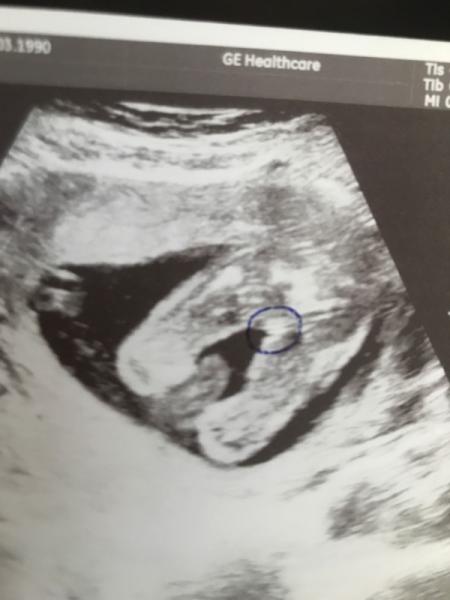

Was meint ihr? Junge oder Mädchen? :)

Sieht aus wie ein Mädchen

Ich würde auch auf Mädchen tippen

Ich würde auch Mädel sagen...

Würde auch denken ein Mädchen

noch ne stimme für Mädchen